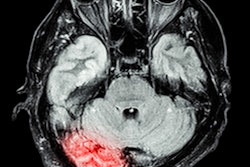

The purchase makes Blackford a wholly owned subsidiary of Bayer and will boost Bayer's digital medical imaging position in the market, the company said.